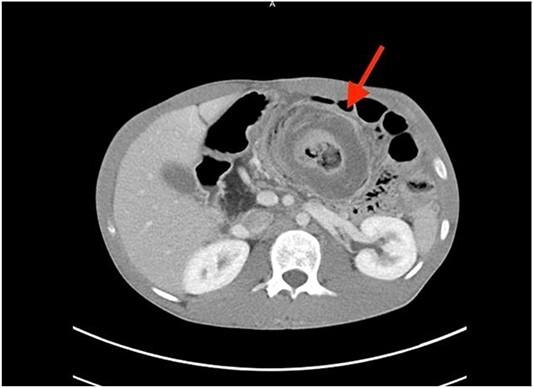

Intussusception, an uncommon but potentially severe condition primarily associated with infants and young children, can also present in adults, posing distinct challenges in diagnosis and treatment. This report presents the case of a 22-year-old male with cystic fibrosis, who developed intussusception due to severe constipation in his distal gastrointestinal tract. The patient's initial presentation included abdominal pain, constipation, and abnormal laboratory results. Computed tomography scans revealed intussusception affecting the ascending colon and cecum, necessitating surgical intervention and subsequent bowel resection. In adults, the presence of intussusception often triggers suspicion of underlying pathological lead points. However, in this instance, the root cause was attributed to cystic fibrosis induced constipation. Current evidence suggests limited efficacy with conservative treatment, with bowel resection being the most definitive treatment option. Further research is warranted to establish comprehensive guidelines for managing this uncommon condition, particularly when intertwined with cystic fibrosis.

肠套叠是一种主要发生于婴幼儿的罕见但可能严重的病症,在成人中也可出现,给诊断和治疗带来独特挑战。本报告介绍了一名22岁患有囊性纤维化的男性病例,其因远端胃肠道严重便秘而发生肠套叠。患者最初的症状包括腹痛、便秘及异常的实验室检查结果。计算机断层扫描显示升结肠和盲肠发生肠套叠,需要进行手术干预及随后的肠切除术。在成人中,肠套叠的出现常引发对潜在病理性引导点的怀疑。然而,在本例中,根本原因是囊性纤维化导致的便秘。目前的证据表明保守治疗效果有限,肠切除术是最确切的治疗选择。有必要进行进一步研究,以制定针对这种罕见病症的综合管理指南,尤其是当它与囊性纤维化交织在一起时。